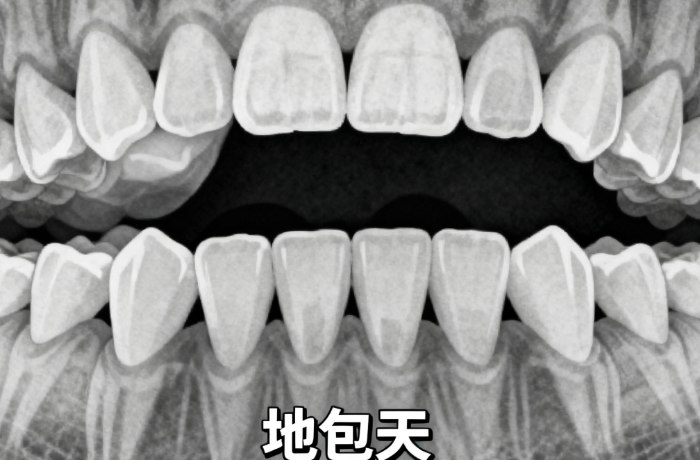

(1)適用人群:適合各類復(fù)雜錯頜畸形,特別是需要精細(xì)控制牙齒移動的病例

(1)適用人群:輕中度錯頜畸形,對美觀要求較高的成年患者